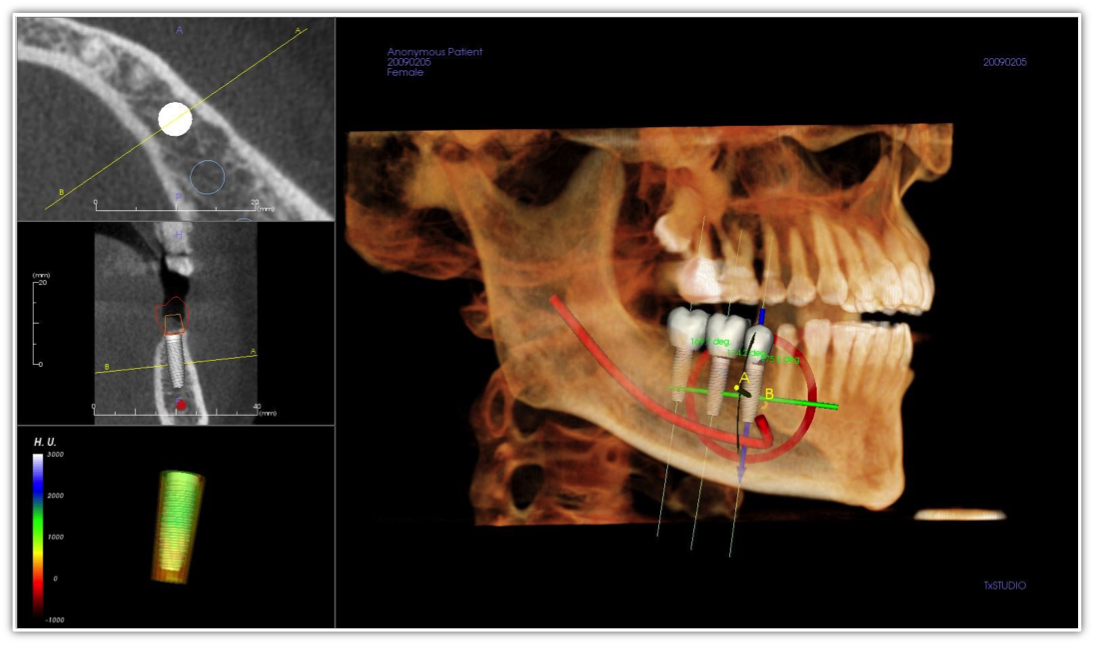

Patient safety and comfort too should be factored into the technology decision. For instance, the author uses a digital x-ray and imaging system that has a more comfortable intraoral sensor with rounded corners that make it more like a lollipop than a credit card, so it is good for people with different anatomies or a pronounced gag reflex. For patients who cannot tolerate even this intraoral system, an extraoral approach can be taken using cone beam computed tomography (CBCT), which is a useful diagnostic tool for general observation, panoramic x-rays, and is essential for practices that offer implants (Figure 1).

Doctors who have CBCT can use it for anatomic assessment of the airway and adjacent structures, and can thereby identify patients at risk for obstruction. Because these scans also include the jaws, teeth, cranial base, spine, and facial soft tissues, there is an opportunity to evaluate the functional and developmental relationships between these structures13 (Figure 5).

Figure 1. A CBCT scan used in conjunction with implant placement software can help guide successful treatment planning and surgical outcomes.

Figure 1